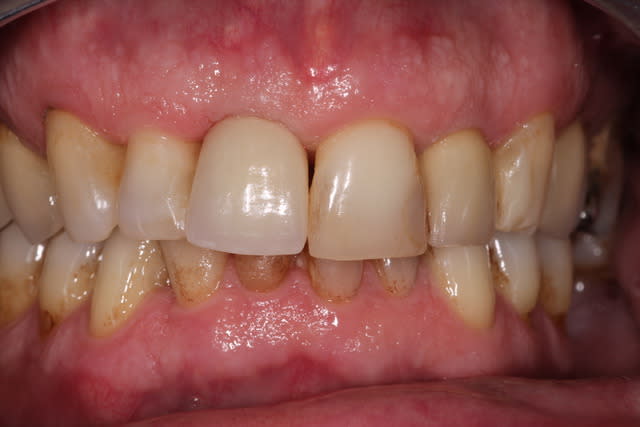

Jour de la pose  7 mois  kkpghj - Eugenol